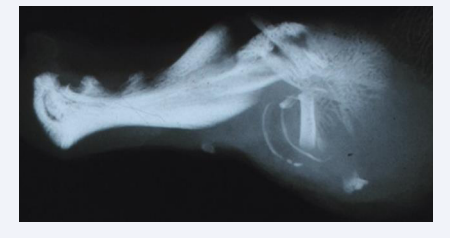

Figure 5 Radiograph taken by a bone sensitive X-ray Machine ( Faxitron Machine) demonstrating a lateral view of a human fetal mandible about  15 weeks of Gestation. The arrows mark the cavities where the primary canine and first molar were located . Between these cavities interdental  alveolar bone has developed.

Figure 5: Radiograph taken by a bone sensitive X-ray Machine ( Faxitron Machine) demonstrating a lateral view of a human fetal mandible about 15 weeks of Gestation. The arrows mark the cavities where the primary canine and first molar were located . Between these cavities interdental alveolar bone has developed.